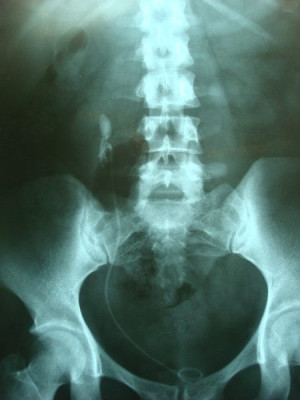

Ureterolitotomía por videolaparoscopía

Envíado por Dr. Juan Carlos Iglesias Guzmán